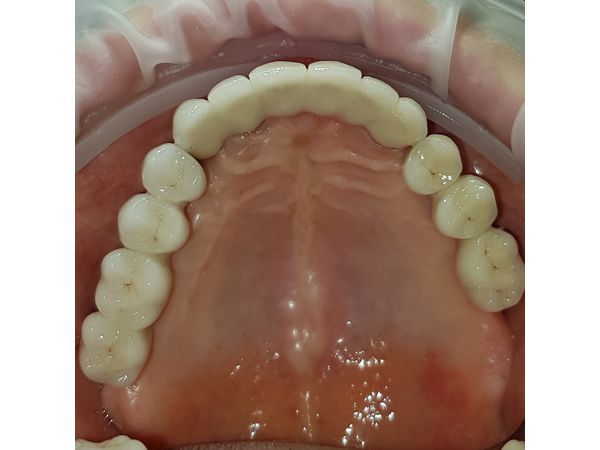

- Несъёмные мостовидные керамические протезы, которые держатся на 6 или 8 имплантатах. Это самый комфортный вариант протезирования, но при этом самый сложный и дорогой.

Здесь представлен случай изготовления несъёмных мостовидных протезов.

Через месяц установлены временные съёмные протезы. Через 4 месяца после приживления имплантатов выполнено протезирование несъёмными мостовидными протезами.

В результате проведённого лечения были достигнуты все требуемые цели:

- восстановлена функция полноценного жевания;

- восстановлена дикция;

- улучшены параметры лица и эстетические параметры;

- улучшено психоэмоциональное состояние пациентки.